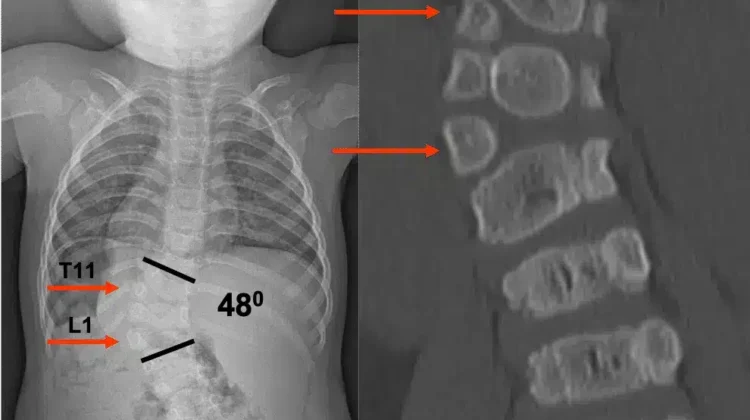

2. الأشعة السينية

تُعتبر الوسيلة الأساسية لتحديد مكان الانحناء وحجمه، وتساعد على متابعة تطور الحالة مع مرور الوقت.